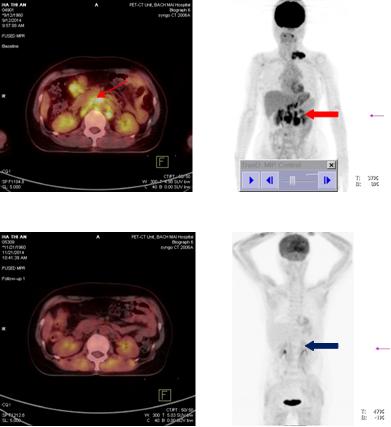

Bệnh nhân được chụp PET/CT nhằm mục đích đánh giá giai đoạn bệnh cho thấy: Hình ảnh tăng hấp thu dược chất phóng xạ tại hạch thượng đòn trái, thành dạ dày, cổ xương đùi phải, và hạch ổ bụng.

Hình 3: Hình ảnh dày thành dạ dày, tăng hấp thu 18F-FDG, max SUV: 3,74 (mũi tên đỏ).

Hình 4: Hình ảnh nhiều tổn thương di căn hạch ổ bụng tăng hấp thu 18F-FDG, kích thước từ 2,1- 8,8cm, max SUV: 8,52 (mũi tên vàng)

Hình 5: Hình ảnh tăng hấp thu 18F-FDG hạch thượng đòn trái, nhiều hạch kích thước 1,5-2,5 cm tạo thành chùm kích thước 6,2x3,2x3,6cm, max SUV: 8,7(mũi tên đỏ)

Hình 6: Hình ảnh tăng hấp thu 18F-FDG tại xương đùi phải. Max SUV:3,2 (mũi tên đỏ)

Trước điều trị: Hình ảnh hạch vùng thượng đòn trái trước điều trị (mũi tên đỏ)

Sau điều trị: Hình ảnh hạch vùng thượng đòn sau điều trị 3 chu kì hóa chất: hạch thượng đòn trái đã tan biến (mũi tên xanh: không còn tổn thương)

Hình 8: Hình ảnh so sánh trước và sau điều trị 3 chu kì hóa chất

Trước điều trị:Hình ảnh hạch ổ bụng trước điều trị 3 chu kì hóa chất

Sau điều trị: Hình ảnh hạch ổ bụng sau điều trị 3 chu kì hóa chất: Hạch ổ bụng đã tan hết. (Mũi tên xanh: không còn tổn thương)

Hình 9: Hình ảnh so sánh trước và sau điều trị 3 chu kì hóa chất